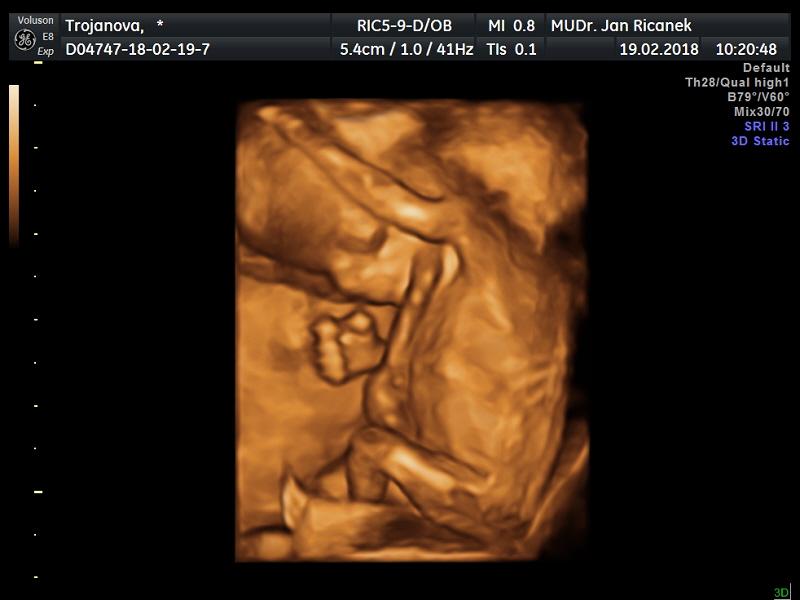

@dailik holky genetika nezklamala, je to opravdu kluk. Máme 7cm a je to pohodář a ďáblík zároveň. Dělal psí kusy při vyšetření. Děsí mě ta omotaná pupeční šňůra ale věřím mu, dle utz jsme dnes 13+1. léky vysazuji, večer už brát nemám .U vás to bude v pořádku a doporučuji vzít s sebou partnera je to nádhera-já ho bohužel s sebou neměla , protože má angínu ale všechny fotečky mám na dvd tak jsem mu je hned pustila